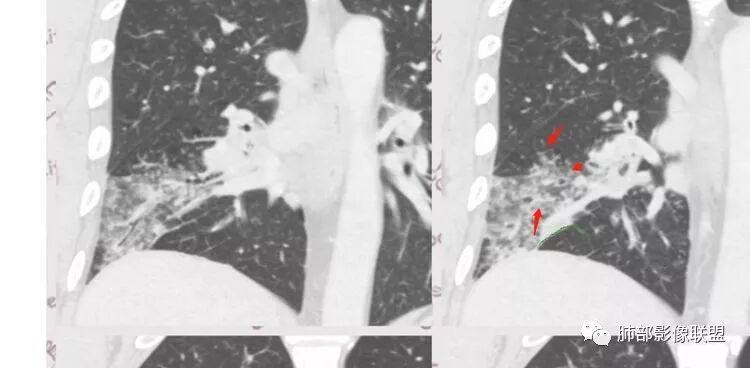

但是问题来了:淋巴结

南边:

右肺门区淋巴结增大,融合,密度均匀,均匀强化

符合这个特点的:结核?淋巴瘤?转移瘤?

淋巴结我觉得目前的特点:淋巴瘤?结核?

这个是前基底段的,支气管扩张区域的,前面提了,独立出来

支气管没看到明显的堵塞

但是应该是与受压局部狭窄,导致远端引流不畅有关